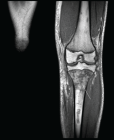

Acute osteomyelitis (AOM) is defined as an inflammation of the bone secondary to infection. Among the most common complications of AOM is the development of a periosteal abscess and the extension of the focus locally to muscle (pyomyositis) and/or joint (osteoarthritis). However, complications with much lower incidence have been described, including deep vein thrombosis (DVT) and septic pulmonary embolisms (SPE), mainly associated with S. aureus infections. The AOM + DVT + ESP triad is a fairly uncommon entity in the pediatric population; however, if it is not diagnosed and treated in time, it implies a high morbidity and mortality. Treatment, which must be early and aggressive, includes targeted antibiotic therapy, anticoagulation, and focused control surgery. In this article, we describe the case of a 14-year-old boy with disseminated staphylococcal infection associated with the triad AOM+ DVT + SPE.